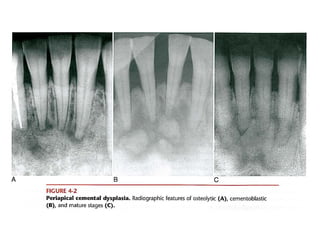

Periapical cemento-osseous dysplasia

Cementa-osseous dysplasia. low-power photomicrograph showing fragments of

cellular fibrous connective tissue conta in ing scattered trabeculae of bone.

Cementa-osseous dysplasia. High-power photomicrograph showing spicules

of bone and cementum-like hard tissue within moderately ce llular fibrous

connectivet issue, Note the hemorrhage around t he bony trabeculae.